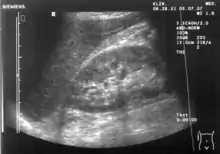

Ultralydsscanning (kan også staves med enkelt s, ultralydscanning) anvendes bl.a. til at tage billeder af fostre samt indre organer. En ultralydsscanner fungerer på samme måde som et ekkolod, som fiskere anvender til at lokalisere fiskestimer. Ultralyd udsendes i impulser fra en transducer og kastes tilbage mod en måler i apparatet, når de møder væv. Man kan derved danne sig et billede af eksempelvis et foster eller et indre organ.

Gravide kvinder tilbydes forskellige former for fosterdiagnostik, hvor ultralydsscanninger indtager en central plads. Omkring uge 13 i graviditeten tilbydes en nakkefoldsscanning, hvor tykkelsen af fosterets nakkefold måles på et ultralydsbillede. Den målte tykkelse bruges i udregningen af risikoen for at fosteret har Downs syndrom. Risikotallet bruges som beslutningsgrundlag for, om der skal foretages en invasiv undersøgelse i form af en fostervandsprøve eller en moderkageprøve. De invasive undersøgelser giver sikkert svar på, om der er kromosomfejl hos fosteret, men de indebærer en risiko for at fremprovokere en abort.

Ca. halvvejs i graviditeten (omkring uge 20) tilbydes en såkaldt misdannelsescanning. På dette tidspunkt er alle fosterets organer dannet, og dermed kan ultralydsbillederne afsløre, om der er misdannelser i lemmer eller organer. Dette giver mulighed for at foretage en abort, hvis fosteret er misdannet på en måde, så det ikke kan overleve uden for livmoderen, eller at tage passende forholdsregler hvis barnet har misdannelser, f.eks. hjertefejl, der kræver behandling umiddelbart efter fødslen. Ved misdannelsesscanningen er det også muligt med en vis sikkerhed at bestemme barnets køn. Det er ikke en del af tilbuddet på de offentlige sygehuse, men som regel gør scanningspersonalet det gerne alligevel.